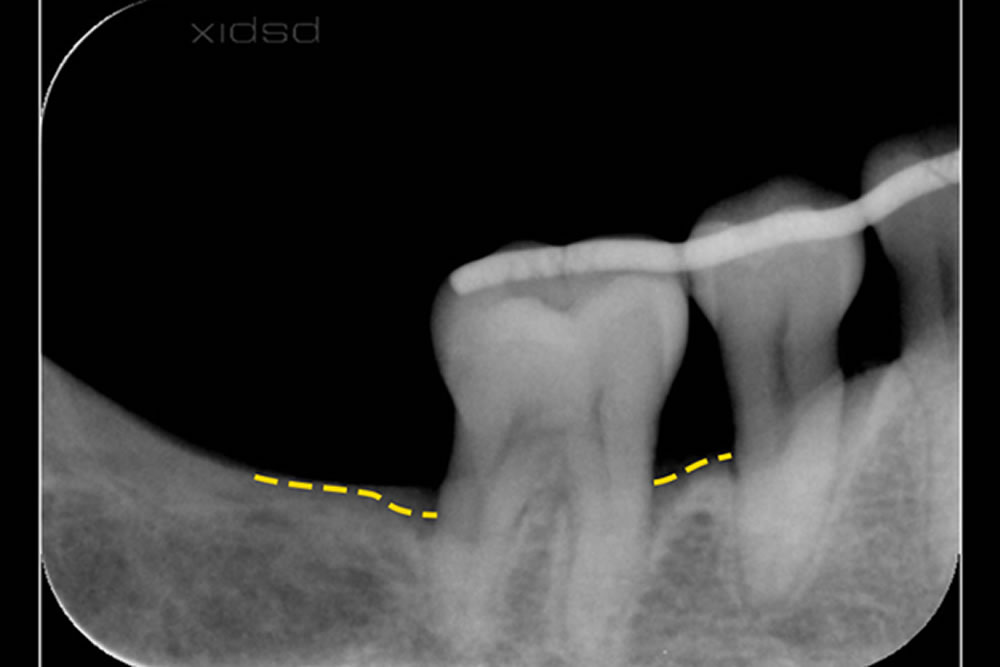

処置は1回のみで、術後は経過観察を続けました。そして治療から1年後、歯ぐきと骨の状態は非常に安定し、まるで再生治療を行ったかのような良好な回復が見られました。現在も健康な状態を維持しています。